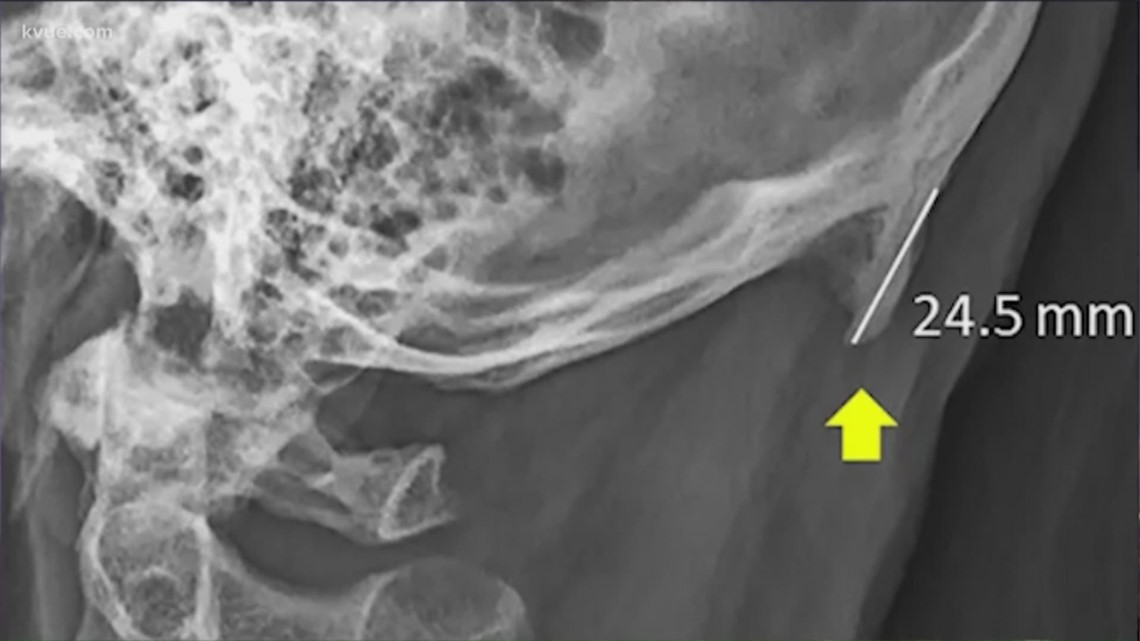

From www.kvue.com

People are growing 'phone horns' due to phone use, researchers say Horns Up Phones Down Horns up, phones down, it can wait could soon be a thing of the. the digital signs have been a staple for entertaining texas drivers while reminding them to be safe while traveling,. you may be hunched over your phone right now, worrying about reports that young people are growing horns on their. the “millennials are growing. Horns Up Phones Down.